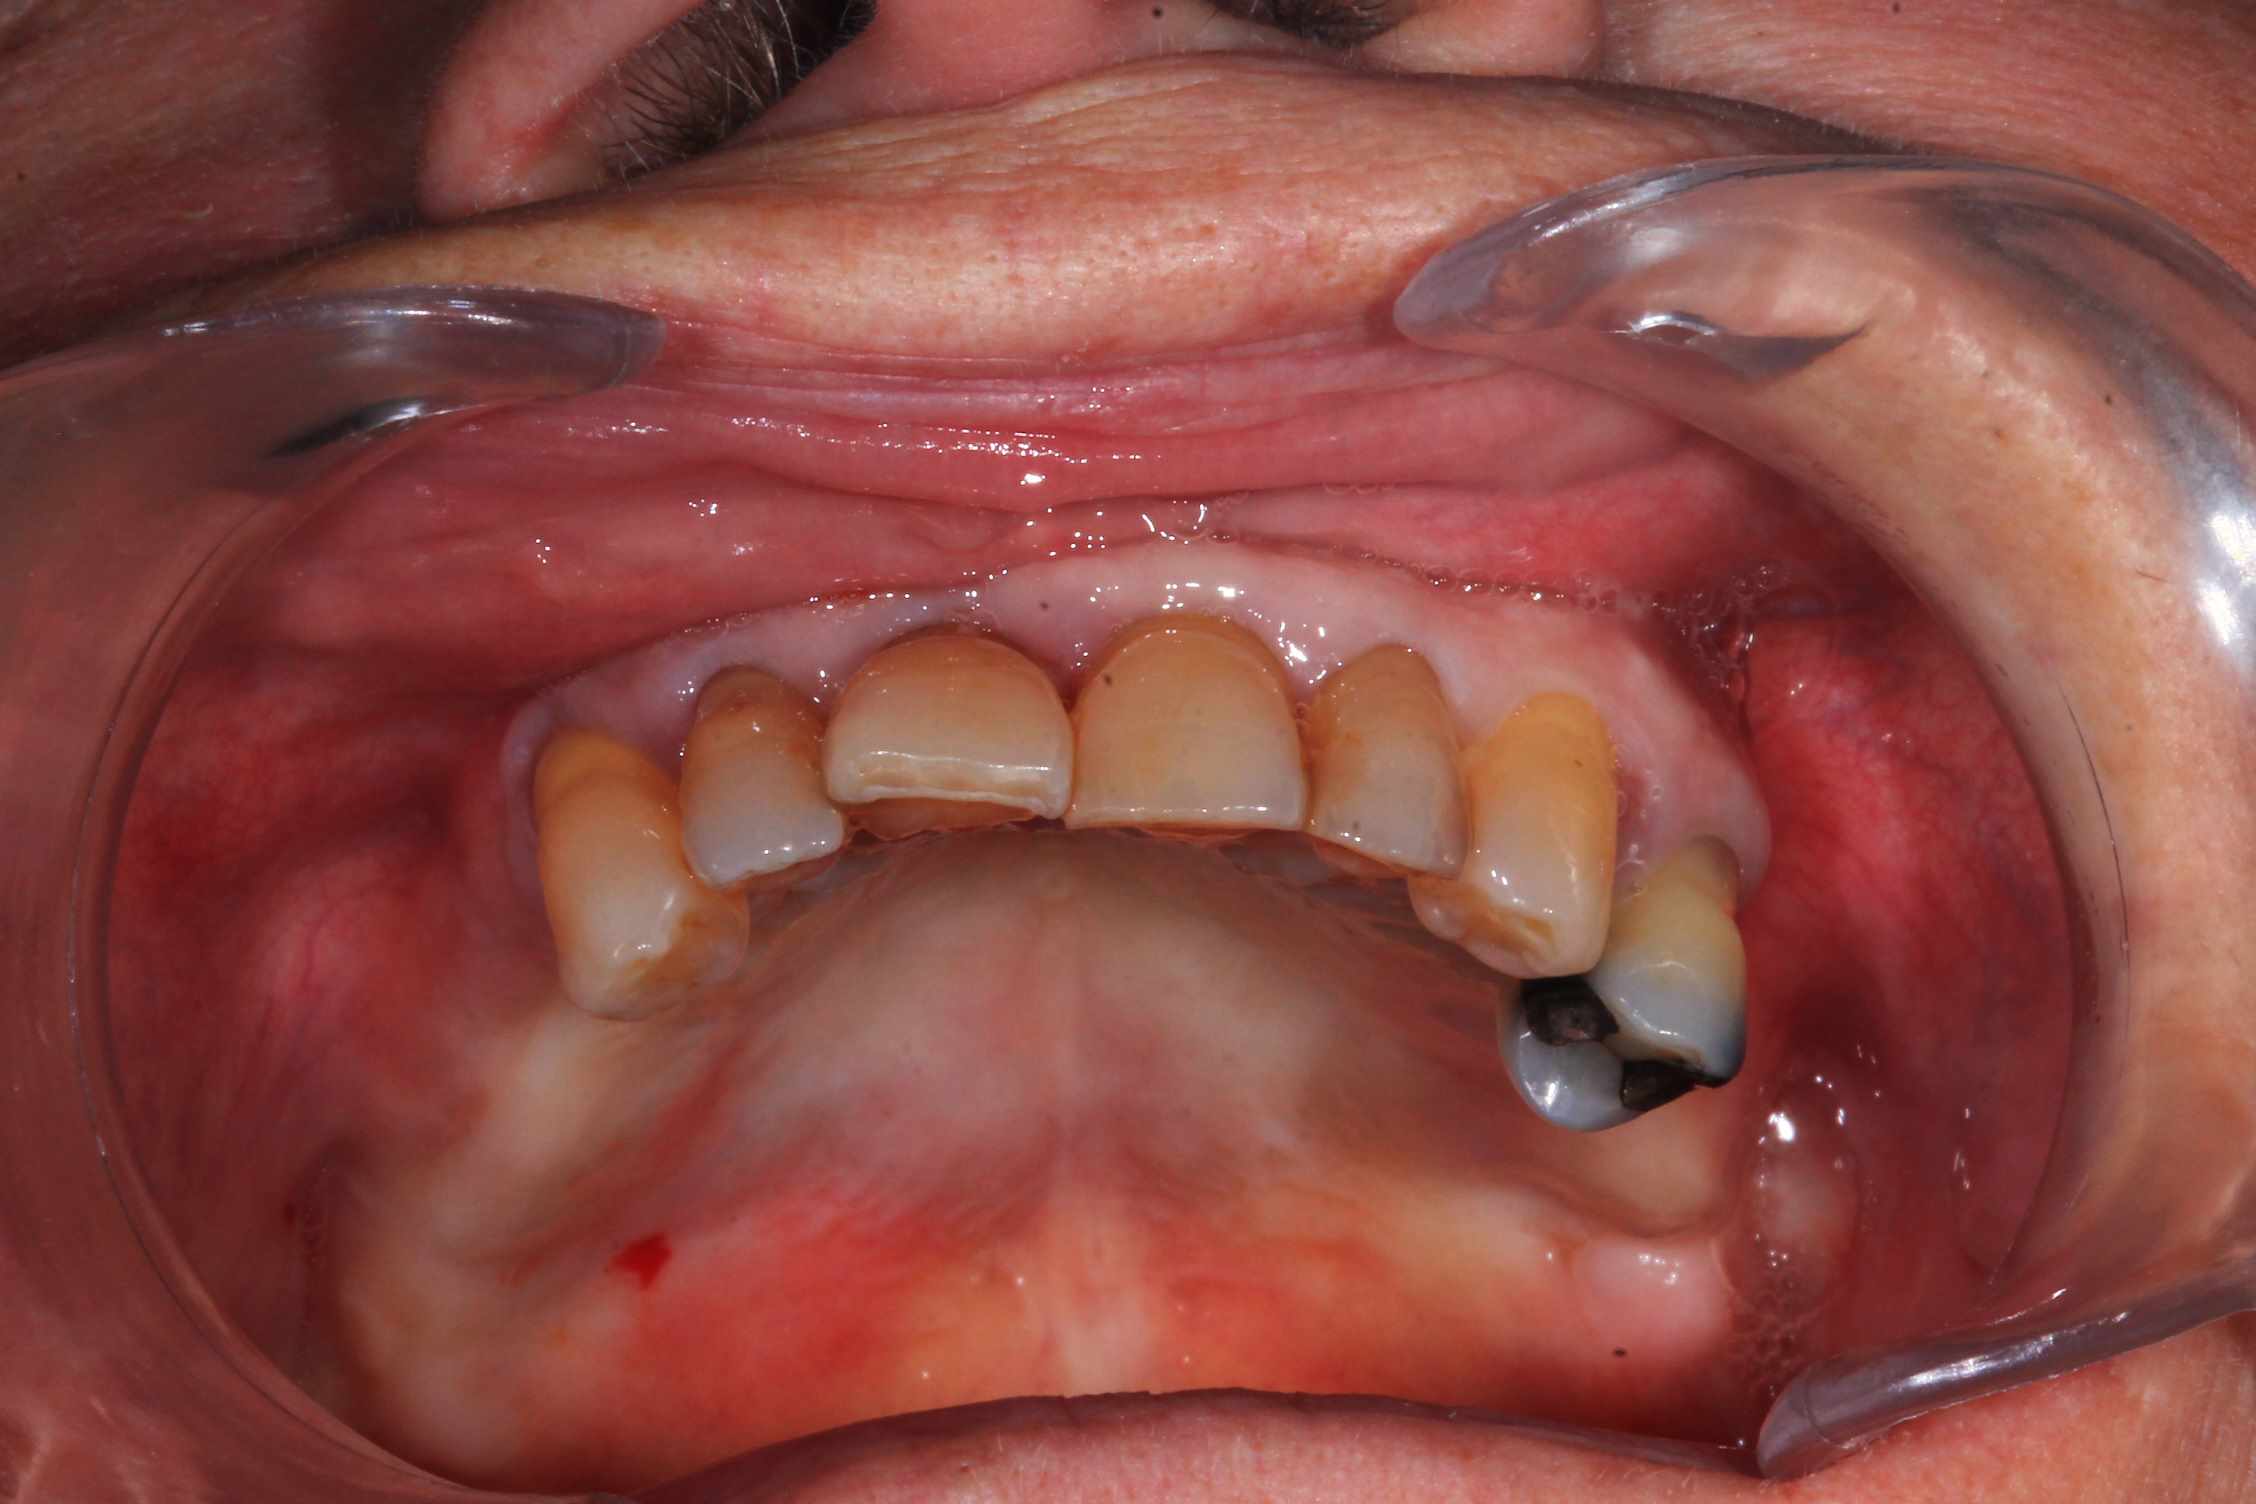

Chir : extraction, implant flapless et pose du bridge imprimé Flexera rosenscrew.

Resultat a une semaine, 3 mois et bridge Full zircone katana maquillé MyIO rosensrew.